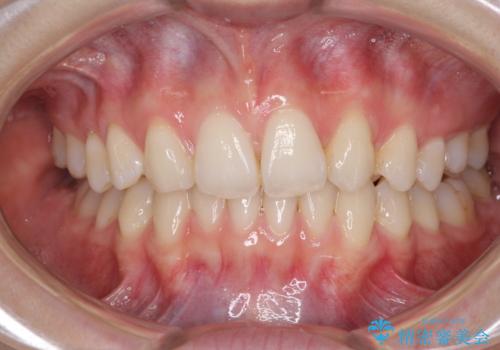

上顎前歯が2本欠損 インビザラインによる叢生の解消

- 深い咬み合わせと前歯のデコボコを気にして来院された患者様です。

上顎前歯2本が欠損しているため、妥協的なゴールを設定しインビザラインで矯正治療を行うこととしました。

上下前歯の大きさのアンバランスにより、深い咬み合わせと奥歯の咬みにくさがなかなか解決されず、治療に長期間を要することとなりました。